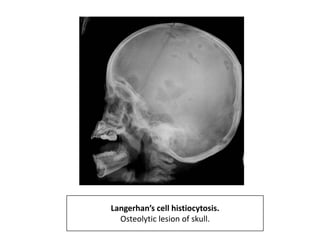

Langerhan’s cell histiocytosis

• It is defined as an intraosseous mass of proliferating

Langerhans cells.

• They are dendritic cells and normally populate the

• Single or multpile lesions restricted to the skeleton

have been termed as eosinophilic granuloma.

• Common during first three decades of life.

• Males are affected more than females.

• The disease usually manifests in skeleton, skin, lung

and lymph nodes.

• In skeleton most common- skull, jaw, vertebral

bodies, ribs, pelvis and long bones.

• X ray-

• Well defined, lytic lesions.

• Cortical involvement may elicit periosteal reaction.

Langerhan’s cell histiocytosis.

Osteolytic lesion of skull.